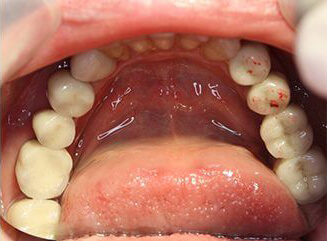

Probleem. Mitmekordsed karioossed kahjustused hammastel, suur hammaste väärarengute tase.

Lahendus. Halva hambaprognoosi tõttu eemaldati ülejäänud hambad ja paigaldati neli hambaimplantaati ülemisse ja alumisse lõualuusse. Implantaadid toetati metallist keraamiliste kroonidega.